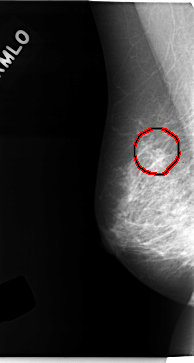

C_0127_1.RIGHT_MLO

RIGHT_MLO LINES 4712 PIXELS_PER_LINE 2512 BITS_PER_PIXEL 12 RESOLUTION 50 OVERLAY

FILE: C_0127_1.RIGHT_MLO.OVERLAY

TOTAL_ABNORMALITIES 1

ABNORMALITY 1

LESION_TYPE MASS SHAPE IRREGULAR MARGINS ILL_DEFINED

ASSESSMENT 4

SUBTLETY 2

PATHOLOGY MALIGNANT

TOTAL_OUTLINES 1

BOUNDARY